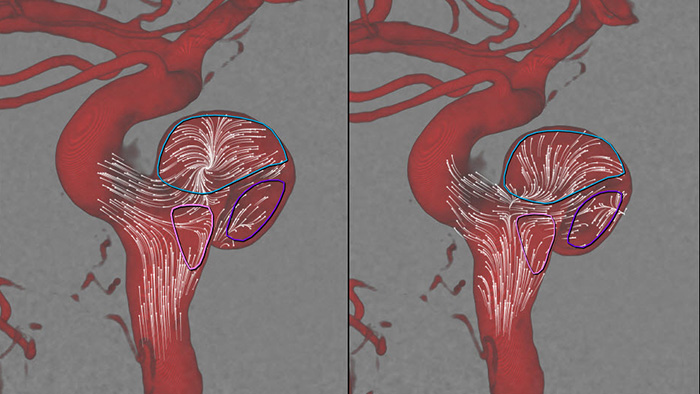

O recurso AneurismFlow ajuda a visualizar e quantificar os padrões de fluxo sanguíneo no vaso principal e no saco aneurismático para obter informações importantes que possam auxiliar a implantação de desviadores de fluxo e outros dispositivos de embolização.